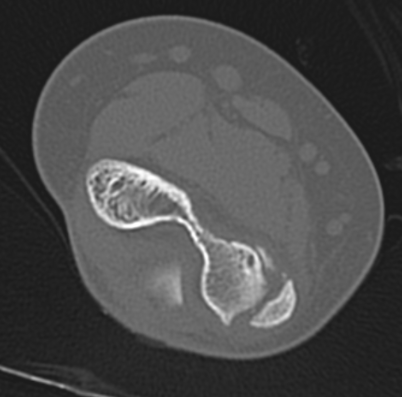

CT